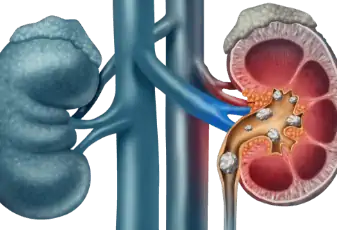

אבנים בכליות

אבנים בכליות - המדריך עם כל המידע הרפואי והמעודכן בגופנו שתי כליות הממוקמות משני צידי עמוד השדרה, בחלקה האחורי התחתון של הבטן. הכליות הן איברים באורך של כעשרה סנטימטרים, צורתן דומה לשעועית ותפקידן לסנן ולסלק חומרי פסולת מן הדם ולהעב